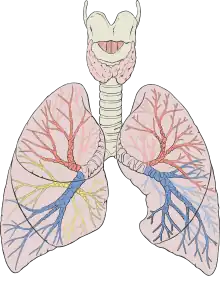

- Both influenza and coronaviruses cause respiratory tract infection that can lead to morbidity and mortality, especially in those who are immunocompromised or who have no existing immunity to the viruses. Indeed, while the COVID-19 should not be taken lightly, influenza is a much bigger problem, but because it is relatively common and has been around for a long time, it does not receive the attention that new viral outbreaks do. The COVID-19 is scary because it is new and we do not know a lot about it yet. New viruses are always scary because we have little to no protective immunity against them and we do not have vaccines. There is work going on to understand and develop preventive strategies to deal with this COVID-19 threat. However, universal precautions to limit its spread are very important right now until a new vaccine or another strategy is available.

- COVID-19 seems to spread more easily than flu and causes more serious illnesses in some people. It can also take longer before people show symptoms and people can be contagious for longer.

These differences have led to some confusion about the lethality of SARS-CoV-2. Some experts and media reports describe it as less deadly than SARS-CoV because it kills about 1% of the people it infects, whereas SARS-CoV killed at roughly ten times that rate. But Perlman says that’s the wrong way to look at it. SARS-CoV-2 is much better at infecting people, but many of the infections don’t progress to the lungs. “Once it gets down in the lungs, it’s probably just as deadly,” he says.

SARS-CoV-2, unfortunately, can do both very efficiently. That gives it two places to get a foothold, says Shu-Yuan Xiao, a pathologist at the University of Chicago, Illinois. A neighbour’s cough that sends ten viral particles your way might be enough to start an infection in your throat, but the hair-like cilia found there are likely to do their job and clear the invaders. If the neighbour is closer and coughs 100 particles towards you, the virus might be able get all the way down to the lungs, says Xiao.

These varying capacities might explain why people with COVID-19 have such different experiences. The virus can start in the throat or nose, producing a cough and disrupting taste and smell, and then end there. Or it might work its way down to the lungs and debilitate that organ. How it gets down there, whether it moves cell by cell or somehow gets washed down, is not known, says Stanley Perlman, an immunologist at the University of Iowa in Iowa City who studies coronaviruses. - Clemens-Martin Wendtner, an infectious-disease physician at the Munich Clinic Schwabing in Germany, says it could be a problem with the immune system that lets the virus sneak down into the lungs. Most infected people create neutralizing antibodies that are tailored by the immune system to bind with the virus and block it from entering a cell. But some people seem unable to make them, says Wendtner. That might be why some recover after a week of mild symptoms, whereas others get hit with late-onset lung disease. But the virus can also bypass the throat cells and go straight down into the lungs. Then patients might get pneumonia without the usual mild symptoms such as a cough or low-grade fever that would otherwise come first, says Wendtner. Having these two infection points means that SARS-CoV-2 can mix the transmissibility of the common cold coronaviruses with the lethality of MERS-CoV and SARS-CoV. “It is an unfortunate and dangerous combination of this coronavirus strain,” he says.

These differences have led to some confusion about the lethality of SARS-CoV-2. Some experts and media reports describe it as less deadly than SARS-CoV because it kills about 1% of the people it infects, whereas SARS-CoV killed at roughly ten times that rate. But Perlman says that’s the wrong way to look at it. SARS-CoV-2 is much better at infecting people, but many of the infections don’t progress to the lungs. “Once it gets down in the lungs, it’s probably just as deadly,” he says. - What it does when it gets down to the lungs is similar in some respects to what respiratory viruses do, although much remains unknown. Like SARS-CoV and influenza, it infects and destroys the alveoli, the tiny sacs in the lungs that shuttle oxygen into the bloodstream. As the cellular barrier dividing these sacs from blood vessels break down, liquid from the vessels leaks in, blocking oxygen from getting to the blood. Other cells, including white blood cells, plug up the airway further. A robust immune response will clear all this out in some patients, but overreaction of the immune system can make the tissue damage worse. If the inflammation and tissue damage are too severe, the lungs never recover and the person dies or is left with scarred lungs, says Xiao. “From a pathological point of view, we don’t see a lot of uniqueness here.”

And as with SARS-CoV, MERS-CoV and animal coronaviruses, the damage doesn’t stop with the lungs. A SARS-CoV-2 infection can trigger an excessive immune response known as a cytokine storm, which can lead to multiple organ failure and death. The virus can also infect the intestines, the heart, the blood, sperm (as can MERS-CoV), the eye and possibly the brain. Damage to the kidney, liver and spleen observed in people with COVID-19 suggests that the virus can be carried in the blood and infect various organs or tissues, says Guan Wei-jie, a pulmonologist at the Guangzhou Institute of Respiratory Health at Guangzhou Medical University, China, an institution lauded for its role in combating SARS and COVID-19. The virus might be able to infect various organs or tissues wherever the blood supply reaches, says Guan.